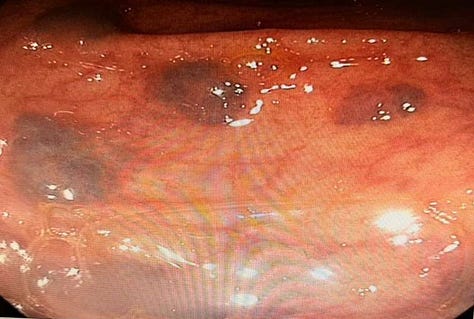

Case 3: A Rare Finding - Blue Rubber Bleb Nevus Syndrome

Case Summary: A series of images showcased the characteristic lesions of Blue Rubber Bleb Nevus Syndrome, a rare vascular disorder.

Key Teaching Points:

•Recognizing the Syndrome: This case served as a great reminder of the endoscopic appearance of this rare syndrome, which is characterized by multiple blue or purple vascular nevi throughout the GI tract and skin.

•Clinical Significance: These lesions can be a source of chronic gastrointestinal bleeding and anemia.